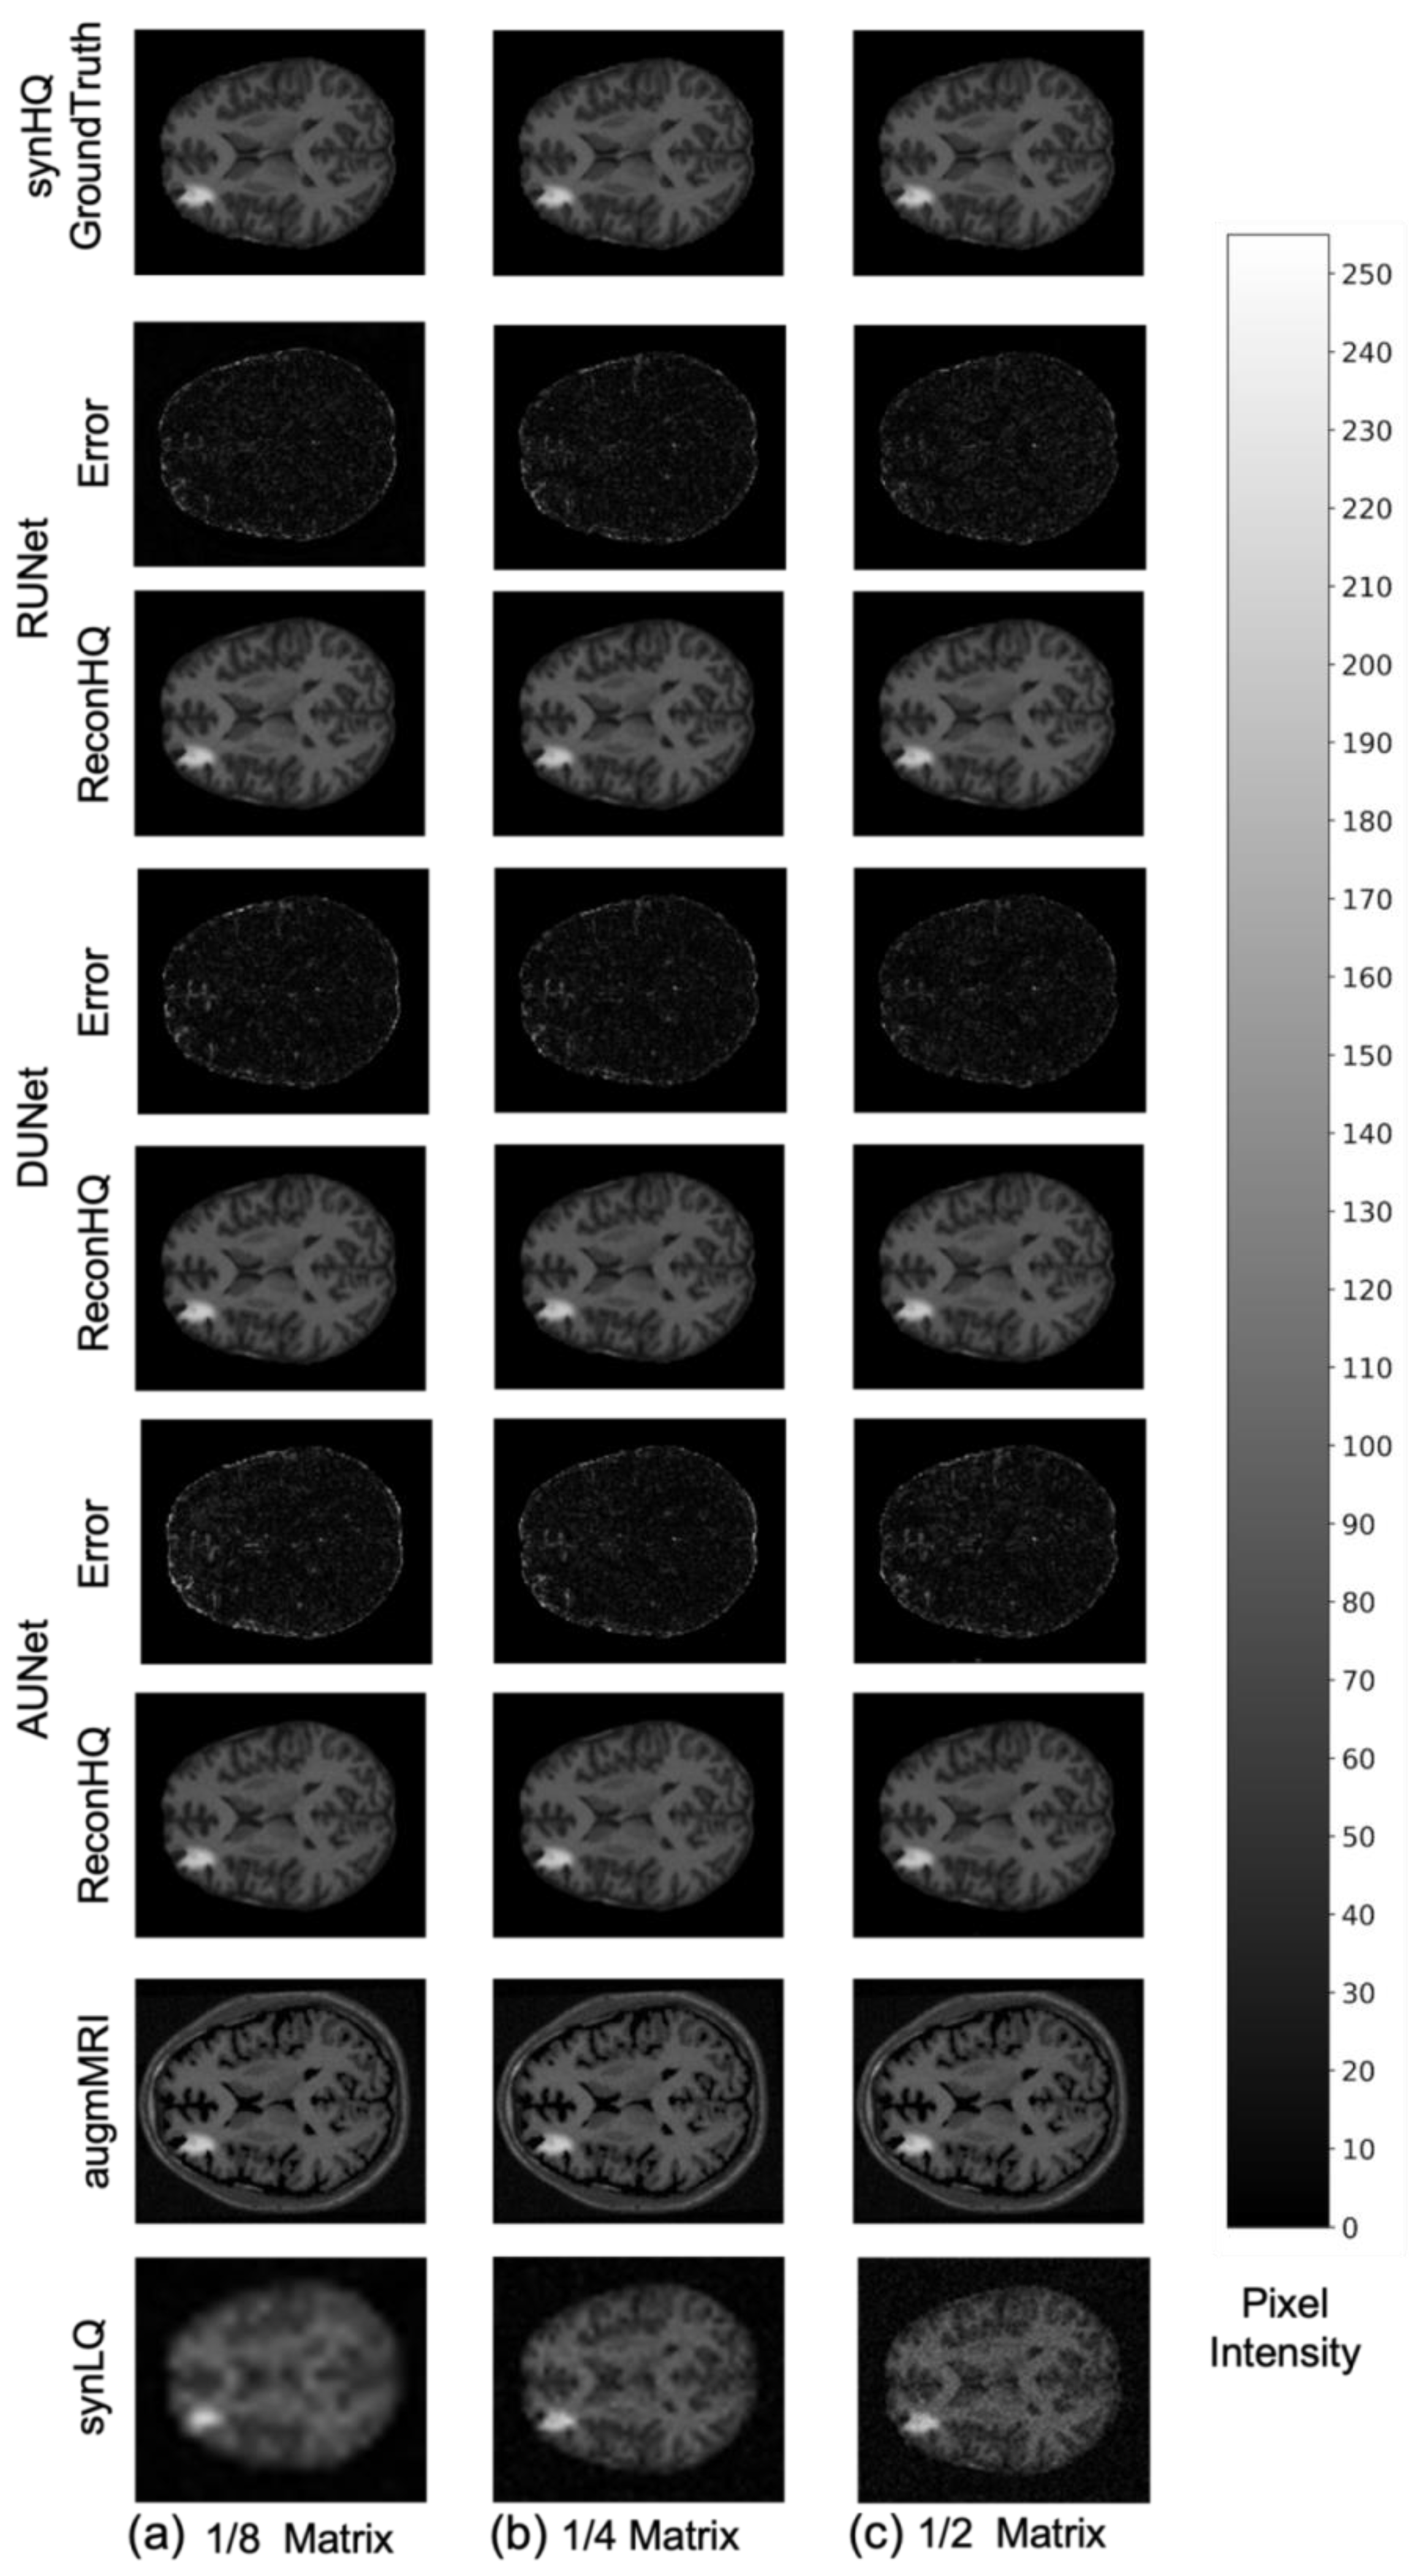

- Two different acquisition scenarios: (a) the With-Priors that mimic studies that entail the collection of both an LQ image and its complementary high quality prior to upscale the image to a corresponding HQ target, (b) the WithOut-Priors that mimic studies that entail the collection of only a single LQ Image to upscale the image to a corresponding HQ target.

- Creation of synthetic training and testing data so we have the same set of LQ images, its complementary HQ prior, and an HQ image (ground truth). In addition, hyperintense lesions of random intensity, size, and position were added to increase the variability in the images.

- The collected LQ Images were truncated to three smaller matrix sizes to mimic studies where the acquisition matrix sizes are small. We train the networks to upscale these images in two acquisition scenarios.